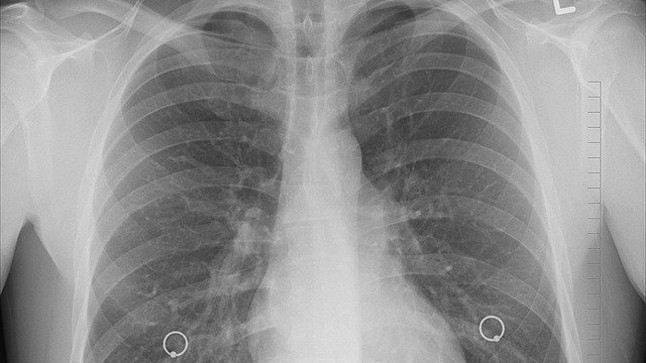

De entre todas las presentaciones identificadas, cinco destacaron por encima del resto. Tal y cómo se recoge en Epidemiology & Infection, durante los dos meses de duración del estudio los investigadores de 'Siesta' identificaron, de manera retrospectiva, 45 miopericarditis aguda (0,71 por ciento),  ocho síndromes de Guillain-Barré (0,13 por ciento), 36 neumotórax espontáneos (0,57 por ciento), 45 pancreatitis agudas (0,71 por ciento) y 16 meningoencefalitis agudas (0,25 por ciento).

De acuerdo con esta comparación, el síndrome de Guillain-Barré es 4,33 veces más común en los enfermos de Covid-19 que en los pacientes sin SARS-CoV-2, el neumotórax espontáneo es dos veces más habitual y el riesgo de la miopericarditis aguda sube 45 por ciento. Por otro lado, la pancreatitis aguda es menos frecuente y no hay diferencias estadísticas significativas en el caso de la meningoencefalitis aguda.